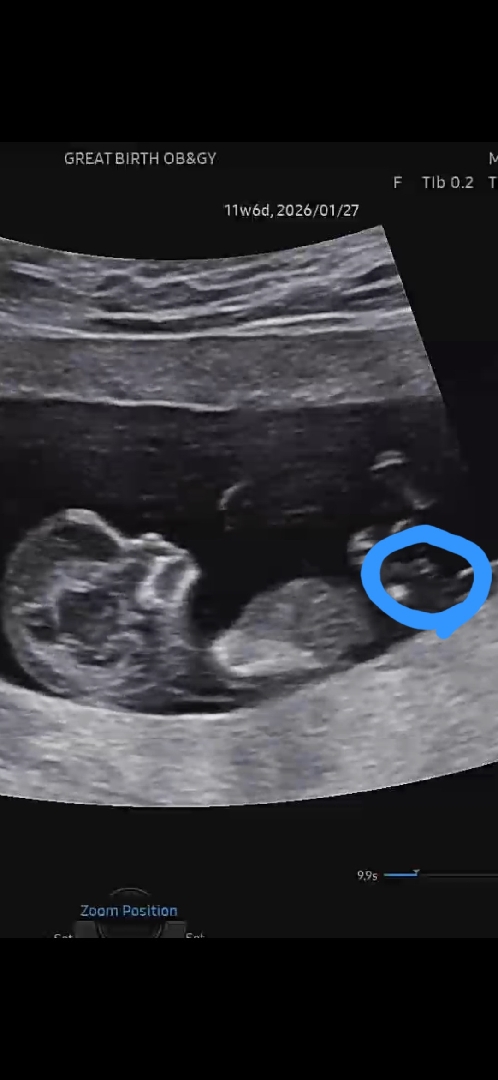

12주차 아들일까요? 딸일까요?

사진에 동그라미 친 부분이 생식기 같은데..아들일까요? 딸일까요??